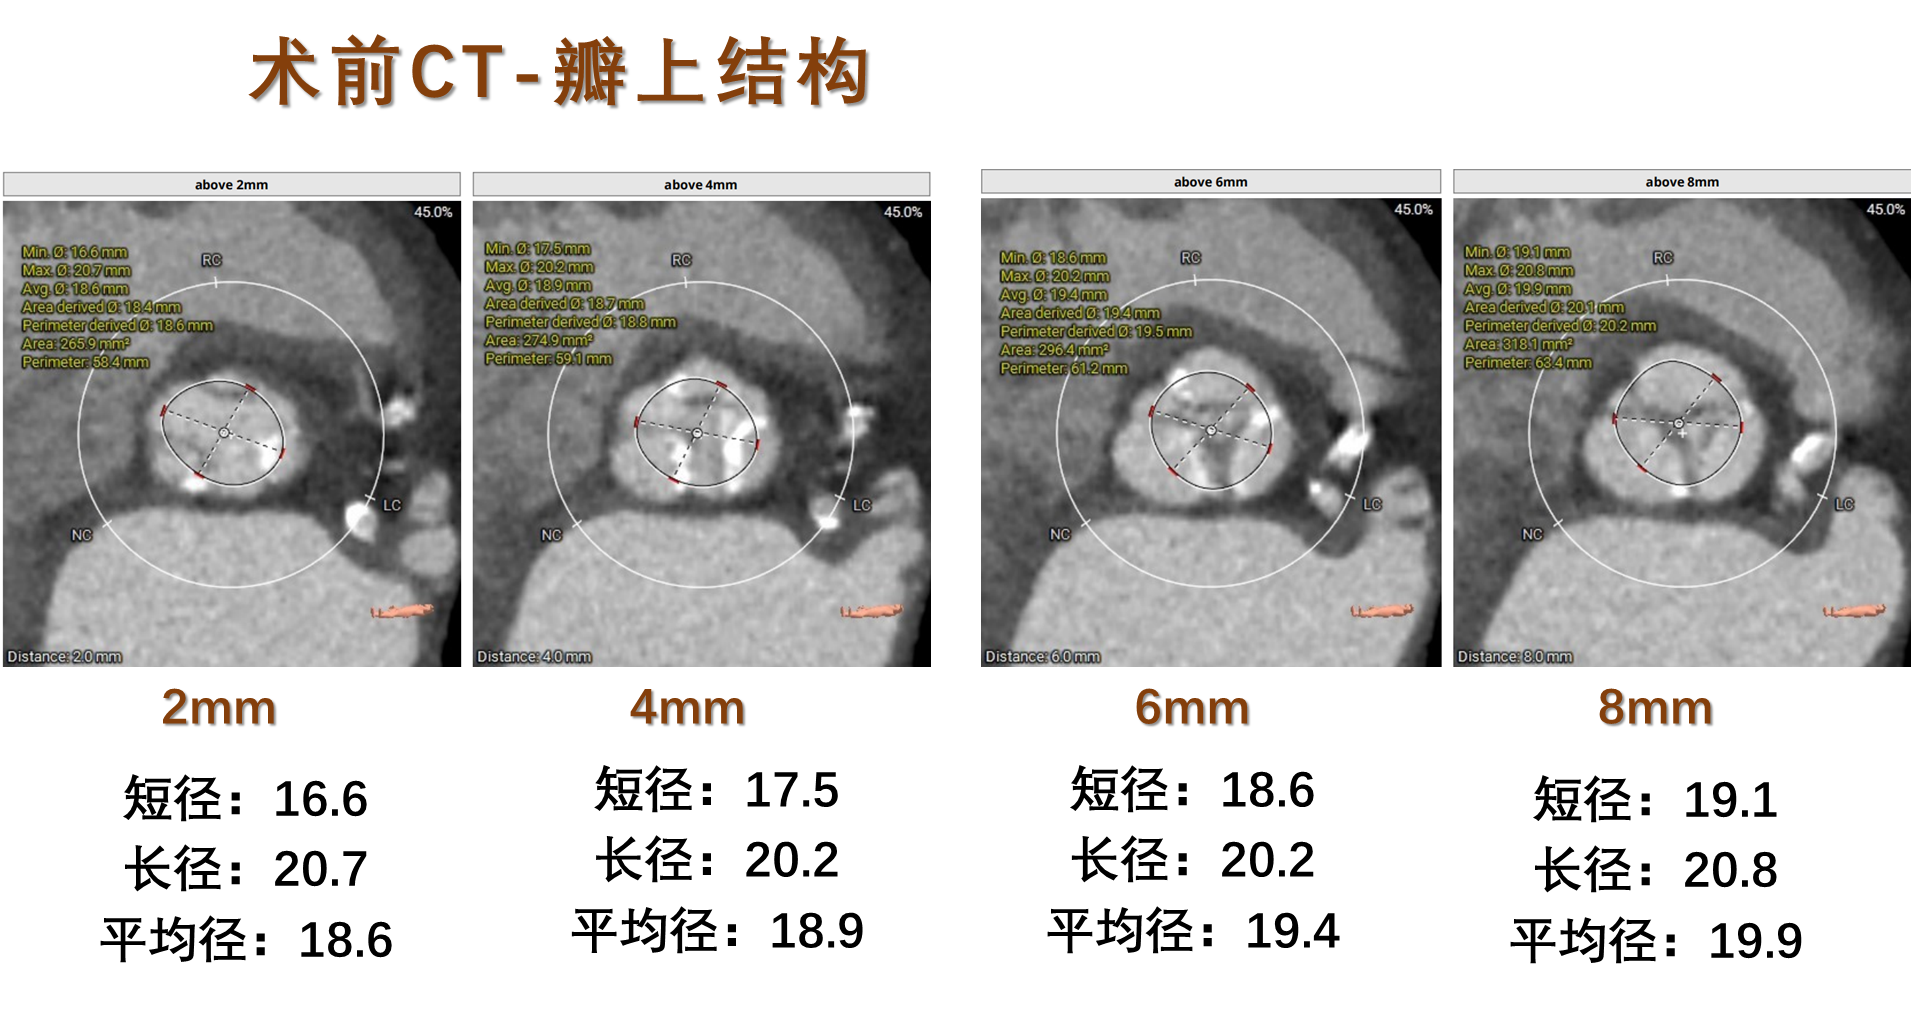

术前CT评估:

瓣膜选择:预装VenusA-Pro 23mm型号瓣膜,18mm球囊预扩,高位释放。